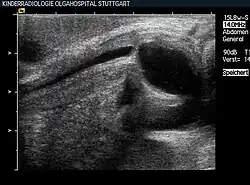

Perinaeale Sonographie bei einem Neugeborenen mit Urethralklappe, deutliche prästenotische Dilatation während der Miktion

Wie bei anderen Organen können auch die ableitenden Harnwege und direkt die Harnröhre von Fehlbildungen betroffen sein, die sich während der Embryonalentwicklung aufgrund verschiedener Faktoren ausbilden. Alle Fehlbildungen der Harnröhre werden, wenn sie Beschwerden bereiten, operativ behandelt und korrigiert.[27]

Ist die Harnröhre nicht angelegt, spricht man von einer Agenesie, ist sie an einer Stelle verschlossen, von einer Atresie. Beide Fehlbildungen sind selten und nur dann mit dem Leben vereinbar, wenn eine andere Harnabflussmöglichkeit bestehen bleibt, etwa ein offener Urachus.[28] Bei manchen, in der Regel männlichen, Neugeborenen bleiben Urethralklappen zurück, die den Harnabfluss behindern.[29]